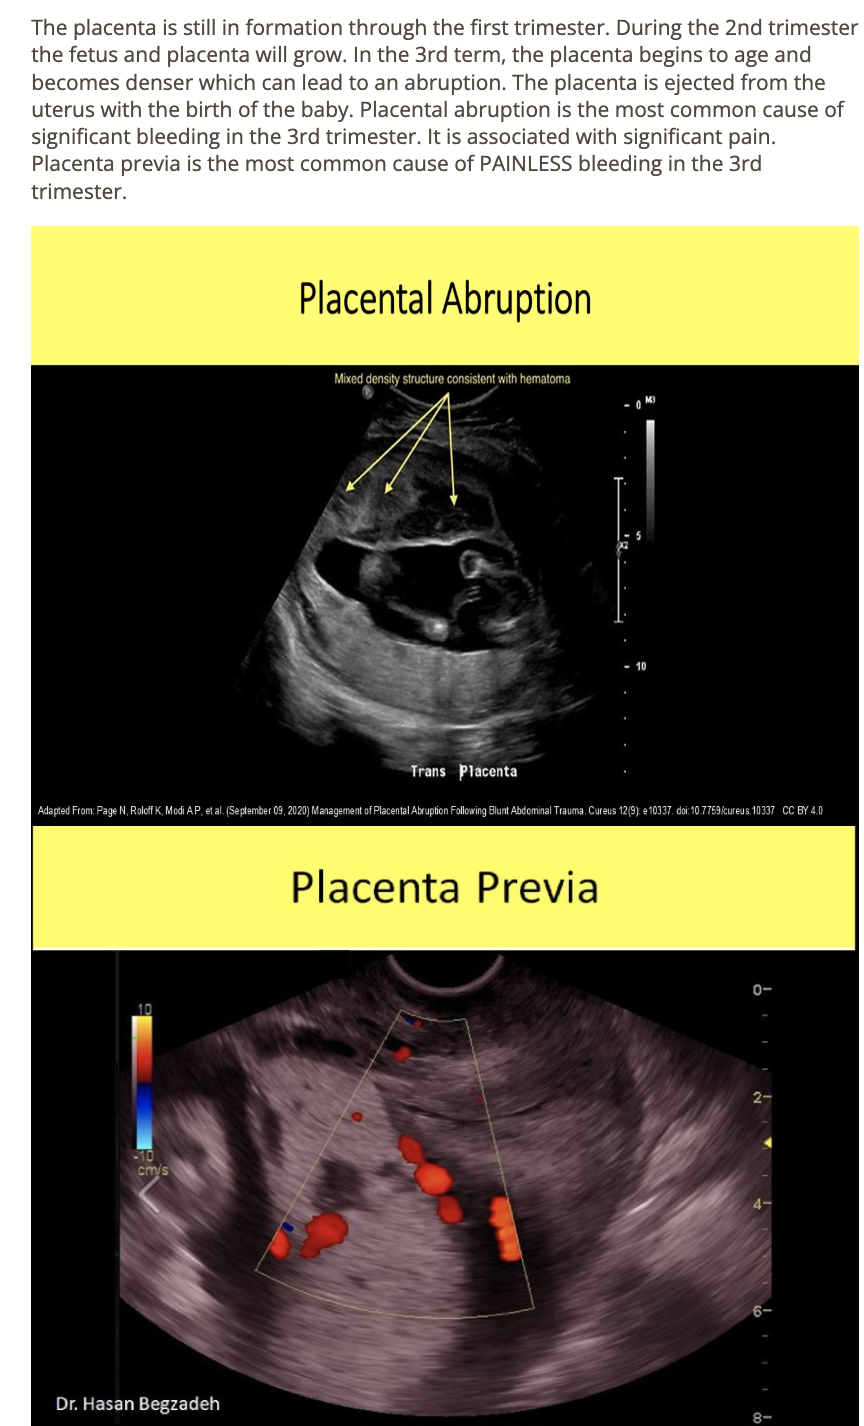

_____ is the most common pathologic cause of significant 3rd trimester bleeding

.

_____ is the most common cause of painless 3rd trimester bleeding

a) placental abruption, placenta previa

b) placental previa, placental abruption

c) placental percreta, placenta accreta

d) placenta accreta, placenta percreta

a pt has 33w gestation w/recent onset intermittent bleeding that is bright red. she does not have any associated pain or cramping

a) placenta previa

b) placental abruption

c) premature rupture of membranes

d) placenta accreta

a pt has 36w gestation w/acute onset of pain + bright red bleeding. she had 2 prior scans that were normal. what is the most common cause for the acute symptoms

a) placenta accreta

b) placenta abruption

c) placenta percreta

d) placenta previa